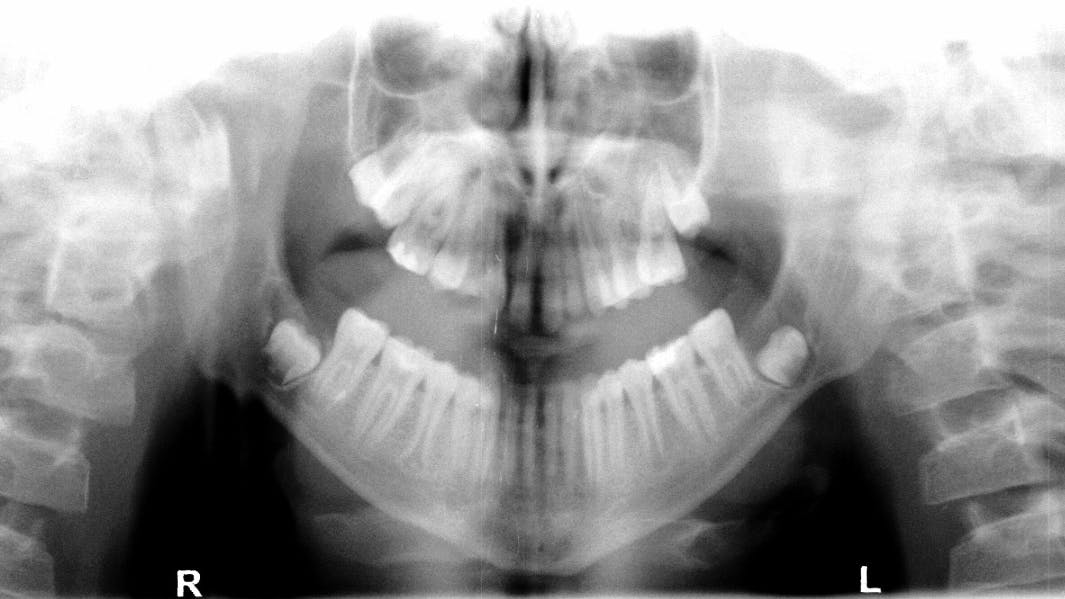

A 14-year-old male was referred to the oral and maxillofacial surgeon to evaluate his lower third molars, each of which appeared on the panoramic radiograph to have significant well-circumscribed, expansile radiolucencies around the impacted teeth.